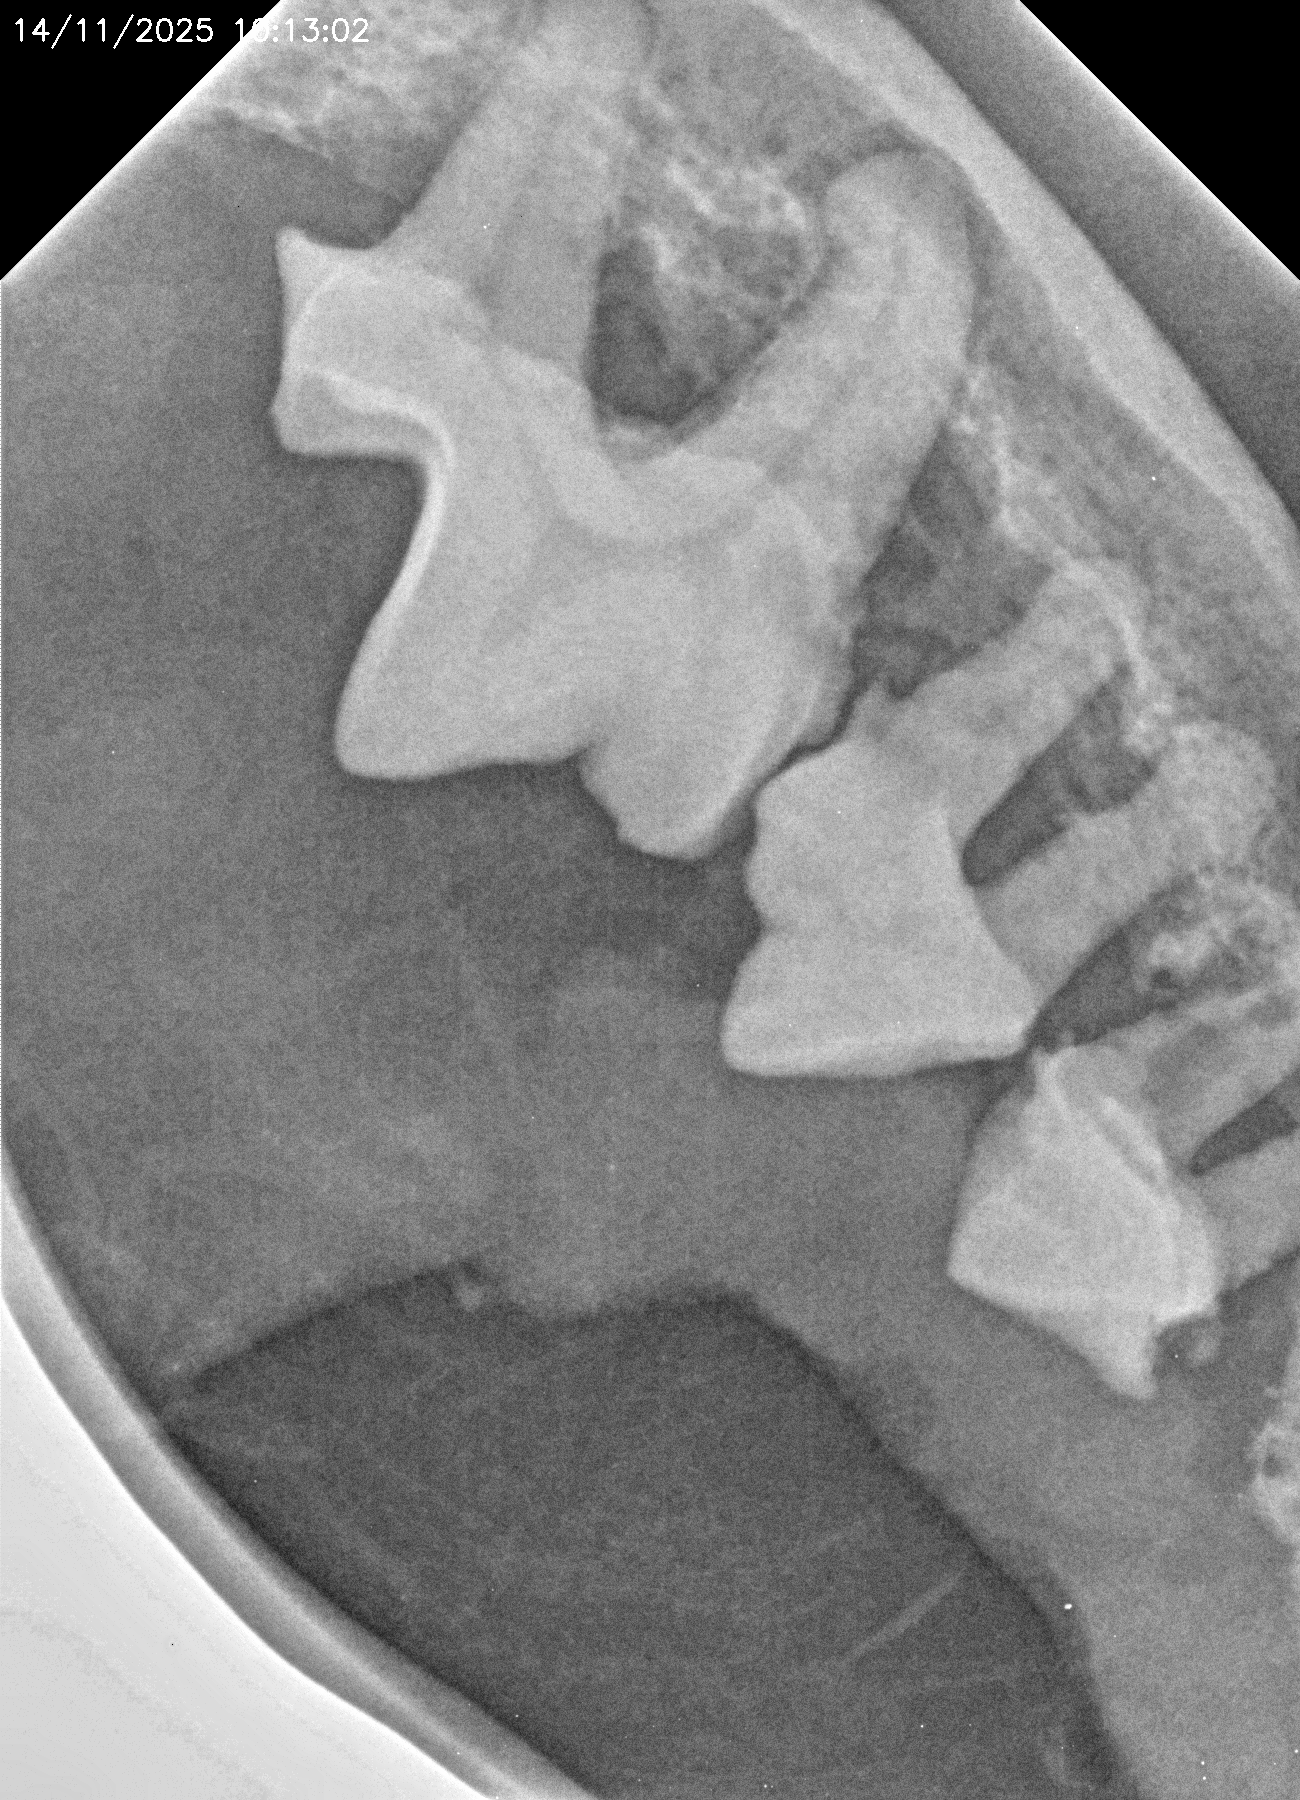

La salud bucal en animales es fundamental para su bienestar general. Los problemas dentales más comunes, como las infecciones bucales, las encías inflamadas o los dientes en mal estado, no solo provocan mal aliento y dolor, sino que pueden causar complicaciones más serias. Cuando se dejan sin tratamiento, las bacterias orales pueden llegar al torrente sanguíneo y afectar órganos importantes como el corazón, los riñones y el hígado.

Al igual que en los humanos, la higiene dental regular es esencial para prevenir enfermedades periodontales y otros problemas dentales. Los animales que sufren de dolor bucal pueden volverse más irritables, perder el apetito y, en algunos casos, experimentar dificultades para comer o masticar.